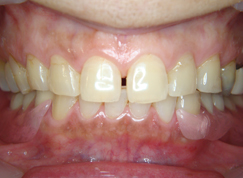

審美入れ歯

入れ歯は残っている歯に針金を引っ掛けるのが欠点。歯に負担をかけ見た目にも入れ歯と分かってしまう。針金を使わない入れ歯なら見た目だけではなく、歯にも負担が少ないですよ。

- 施術前

- 施術後